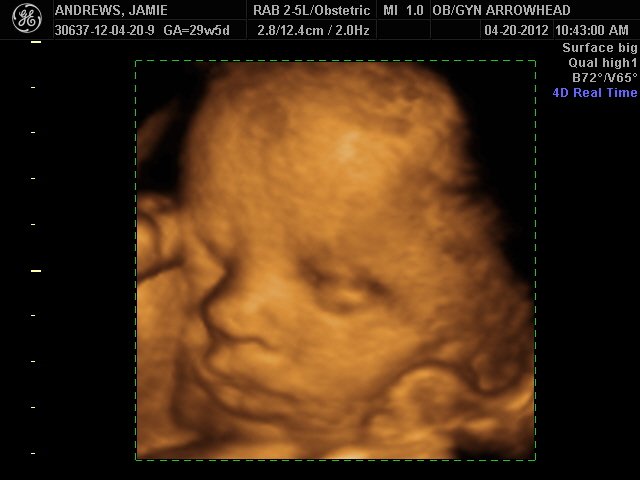

We offer complimentary 3D/4D Ultrasounds to all our OB patients around 30 weeks! The following photos are some examples of our work, shown with permission from our patients.